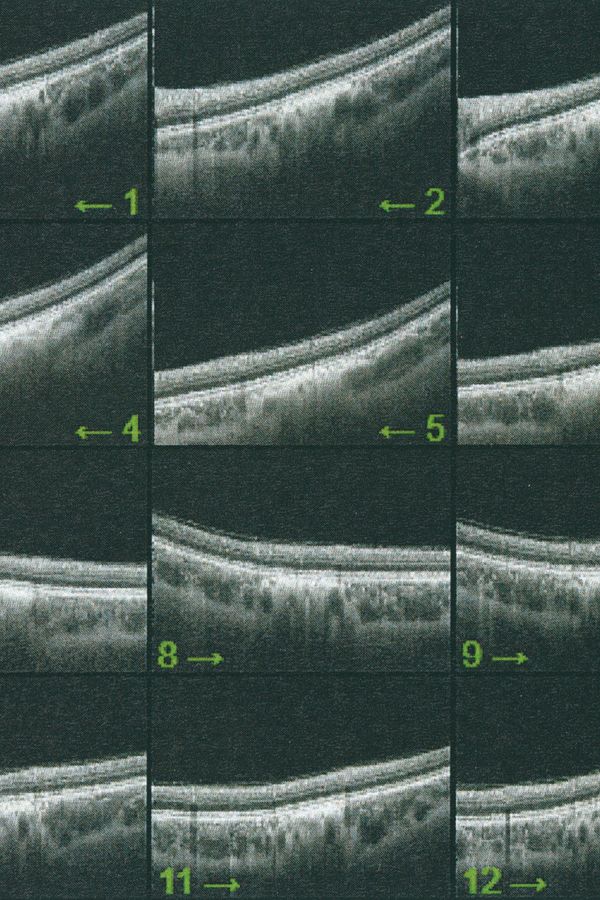

Collirio (Eyewash) is the attempt to demonstrate the non-absoluteness of visual experience and its nature as a situated and yet ambiguous act. It is the path that has allowed me to understand how my fears do not have roots in an unknowable place. The eye is not an unfathomable globe.